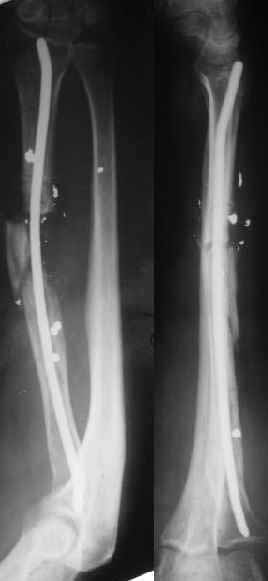

In attachment - image 1 after performed distraction, and 2 - after acute conversion to the nail (5 mm).

It took some efforts to find and ream the canal at the proximal fragment. I hope the patient can leave for the neurosurgery clinic within 3-4 days. Critics/comments are welcome.

Comment It looks like the titanium pin is outside the medullary canal of the intercalary segment. Length and alignment are improved and I guess callus will heal the two fracture sites.

Xray looks good. How do ensure that in such a forearm with adherent soft tissues, you will not cause additional damage during closed reaming?